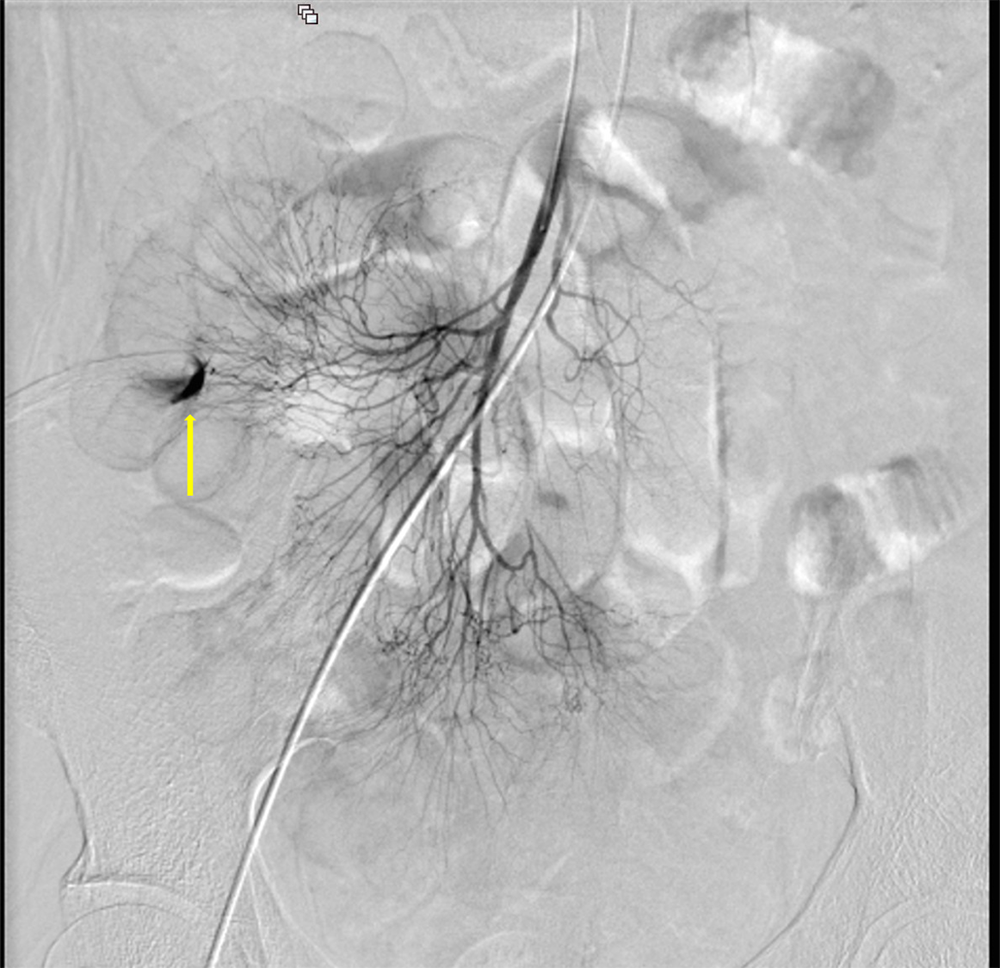

サイトメガロウイルス感染症を背景に下血がみられ消化管出血が疑われた。出血源の精査目的に造影CTが施行された。造影CTにて回腸で造影剤の血管外漏出像がみられ、出血源と考えられた。

造影CT撮像後、直ちに経カテーテル的血管塞栓術を施行し原因血管を金属コイルで塞栓し止血を得ることができた。